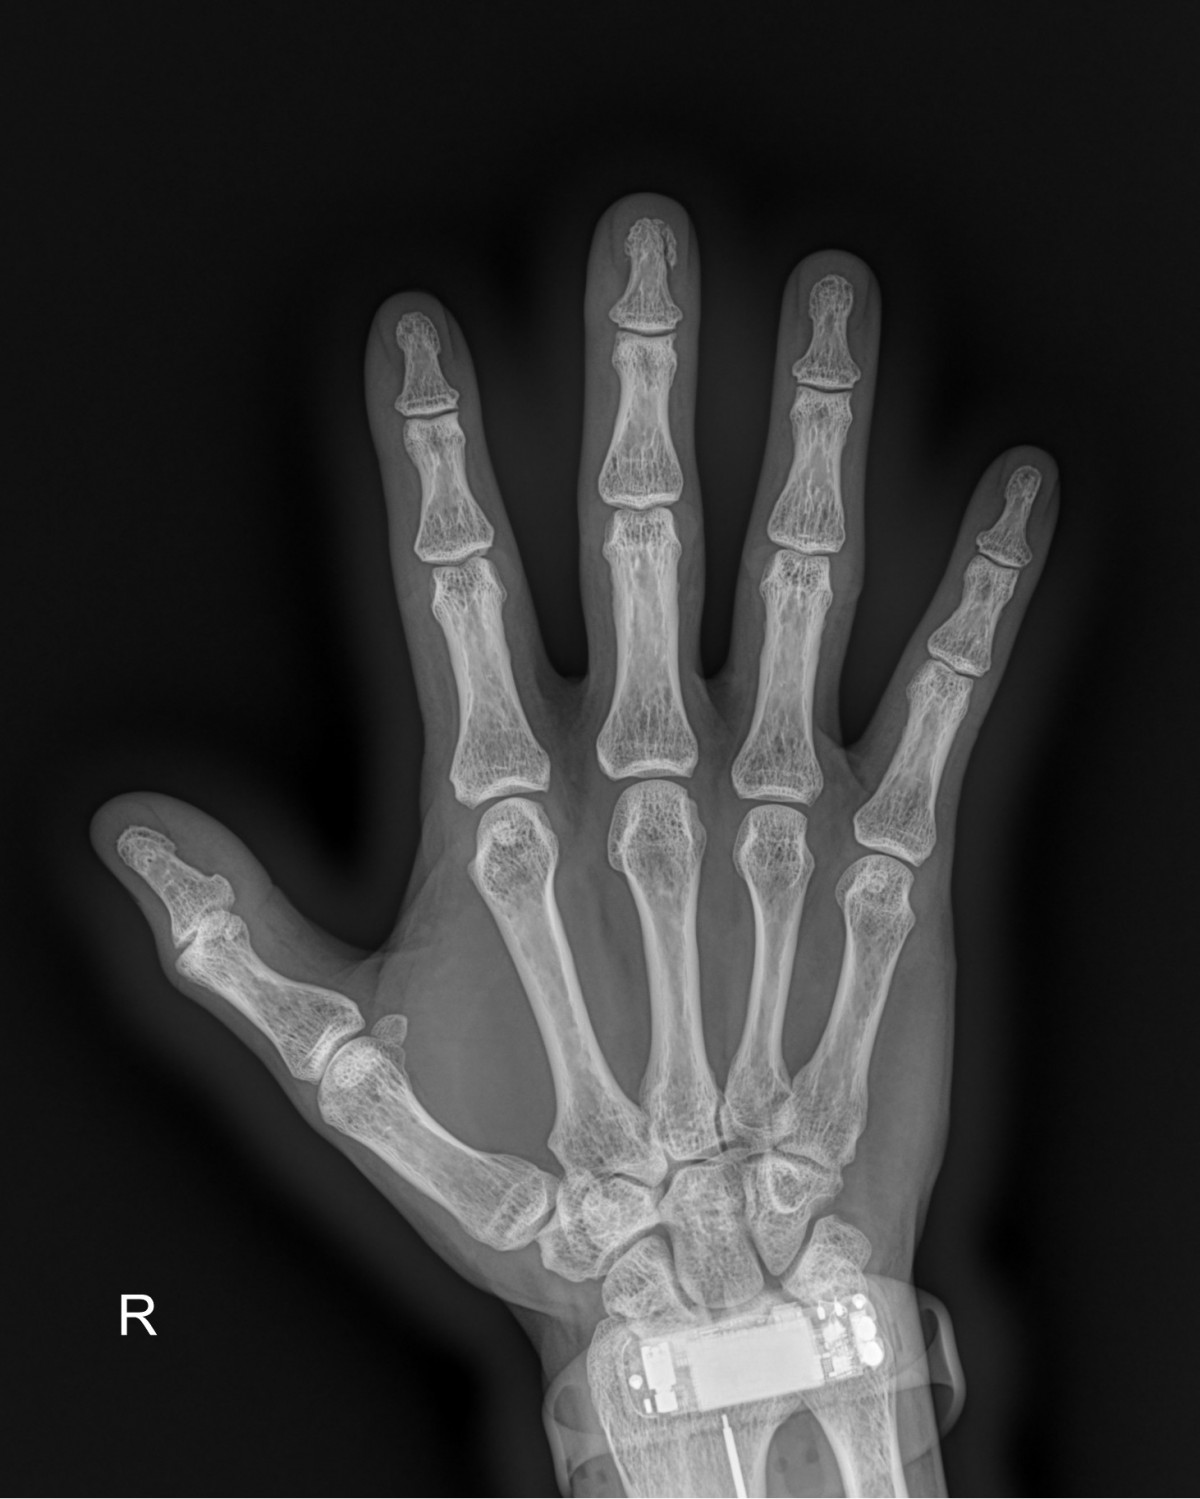

정지영원장님 손가락 골절 한철O 환자

dae765e4d9ac96aee867c9d6292d8784_1758008667_8273.jpg